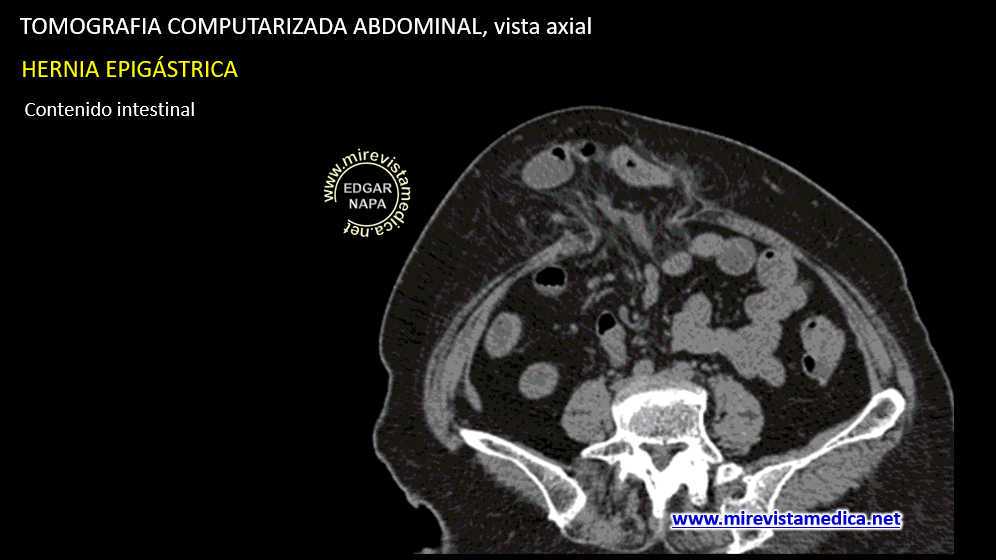

Las hernias de la línea media se producen por la salida de contenido epiploico y / o intestinal a través de un defecto en la línea media anterior.

Las hernias se pueden producer al reposo o por incremento de la presion intrabdominal (maniobra de valsalva

Cuando las hernias no pueden reducirse al acabar la maniobra de valsalva, se denominan no reductible.

En estos casos se debe valorar otros signos como las colecciones dentro del saco herniario o perdida del flujo del asa intestinal herniada, dolor intenso que no cesa; Su presencia la denominaría como hernia incarcerada.